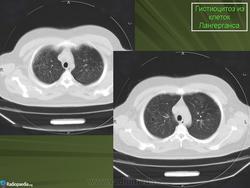

В 5 наблюдениях (21%) из больных с распространенной формой заболевания отмечались изменения в легких в виде обогащения, избыточности легочного рисунка, его деформации по сетчато-петлистому типу, очаговых теней. Корневая и медиастинальная аденопатия отсутствовали. В 1 случае в легких выявлена киста, которая периодически осложнялась нагноением (Рис. 4).

Поражение легочной ткани (рис. 22) свойственно любому возрасту. Часто больные имеют общие симптомы — лихорадку, слабость, реже — кашель, одышку, боли в грудной клетке. На рентгенограммах отмечается деформация и усиление легочного рисунка и микроузловые инфильтративные тени. Поражение костного мозга (с наличием клеток Лангерганса) сопровождается цитопенией периферической крови.

Рис. 22. Поражение легких при Лангер-гансово-клеточном гистиоцитозе.